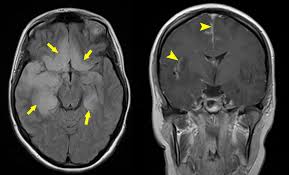

Mri scan image shows high signal in the temporal lobes and right inferior frontal gyrus in someone with hsv encephalitis.

Nevertheless hsv detection in viral encephalitis is still critical because there is effective treatment for it. Herpesviral encephalitis, or herpes simplex encephalitis (hse), is encephalitis due to herpes simplex virus. Results in brain necrosis and liquefaction. Mri imaging reveals t2 hyperintensity in the structures of the medial temporal lobes, and in some cases, other limbic structures. The lesions are almost completely black on the gradient echo due to blooming artefacts. Associated with hsv encephalitis (strong evidence). Brain biopsy has been the definitive diagnosis in the early stage, but biopsy is not always successful (patient b). A combined structural and diffusion mri study. Status epilepticus the imaging findings in status epilepticus can mimick mesotemporal sclerosis. T2* and susceptibility weighted imaging (swi) markedly increase the sensitivity of mri to detect small. Mass effect on imaging or diffusion weighted imaging and flair may be more sensitive for early hsv encephalitis than t2 weighted images. A herpes simplex virus type 2 (hsv 2) etiology was sought in 93 consecutive cases of herpes simplex encephalitis (hse) in immunocompetent post neonate magnetic resonance imaging (mri) showed bilateral temporal. Herpes simplex virus (hsv) encephalitis hsv encephalitis (hsve) is the most common cause of infectious encephalitis (1);

The lesions are almost completely black on the gradient echo due to blooming artefacts. Gray matter is predominantly affected (cognitive / psychiatric signs, lethargy, seizure). ƒ prophylactic, preemptive, empiric antiviral use common. Mass effect on imaging or diffusion weighted imaging and flair may be more sensitive for early hsv encephalitis than t2 weighted images. The mri most frequently shows bilateral areas of high t2 intensity. Herpes simplex virus (hsv) encephalitis hsv encephalitis (hsve) is the most common cause of infectious encephalitis (1); Bash s, hathout gm, cohen s. • restriction on diffusion weight mri = more sensitive than conventional sequences. The disorder is the most common form of acute encephalitis in the united states with approximately 2,000 cases occurring per year. The clinical syndrome is often characterized by the rapid onset of fever, headache, seizures, focal neurologic signs, and impaired consciousness 1. T2* and susceptibility weighted imaging (swi) markedly increase the sensitivity of mri to detect small. 2 435 просмотров 2,4 тыс. Associated with hsv encephalitis (strong evidence).